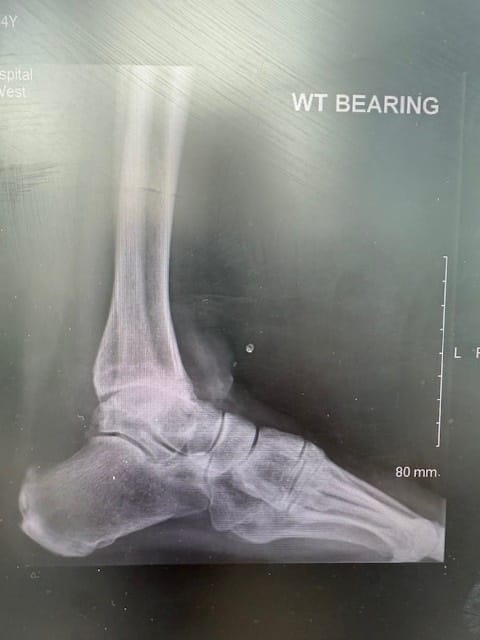

To get further information about her ankle and hindfoot joints we arranged weightbearing X rays which did confirm pronounced osteoarthritis with a varus deformity of both ankle joints, the left again a bit more pronounced than the right. The subtalar and the transverse tarsal joints all looked good.